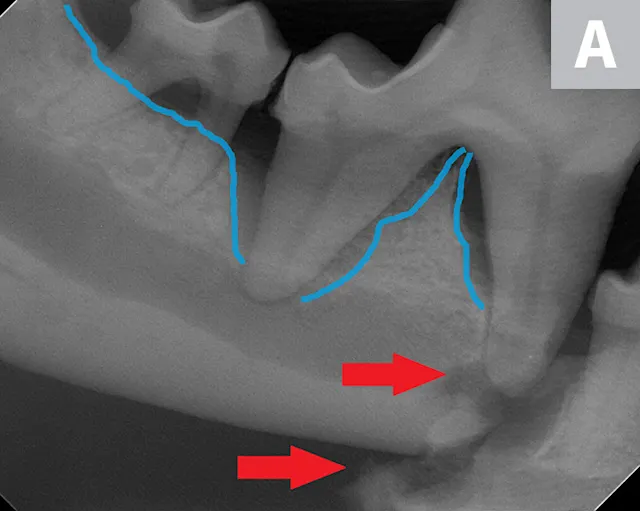

A complete oral examination confirmed stage 4 periodontal disease of numerous teeth (ie, first through fourth maxillary premolars, all maxillary molars, both maxillary canines, all remaining incisors). Dental radiographs confirmed bilateral mandibular fractures at the mesial root of the right mandibular first molar and distal root of the left mandibular first molar (Figures 1 and 2).

Preoperative intraoral dental radiographs of the right (A and B) and left (C) mandibular first molars. There is marked alveolar bone loss secondary to periodontal disease (blue lines), as well as pathologic, iatrogenic mandibular fractures (arrows).